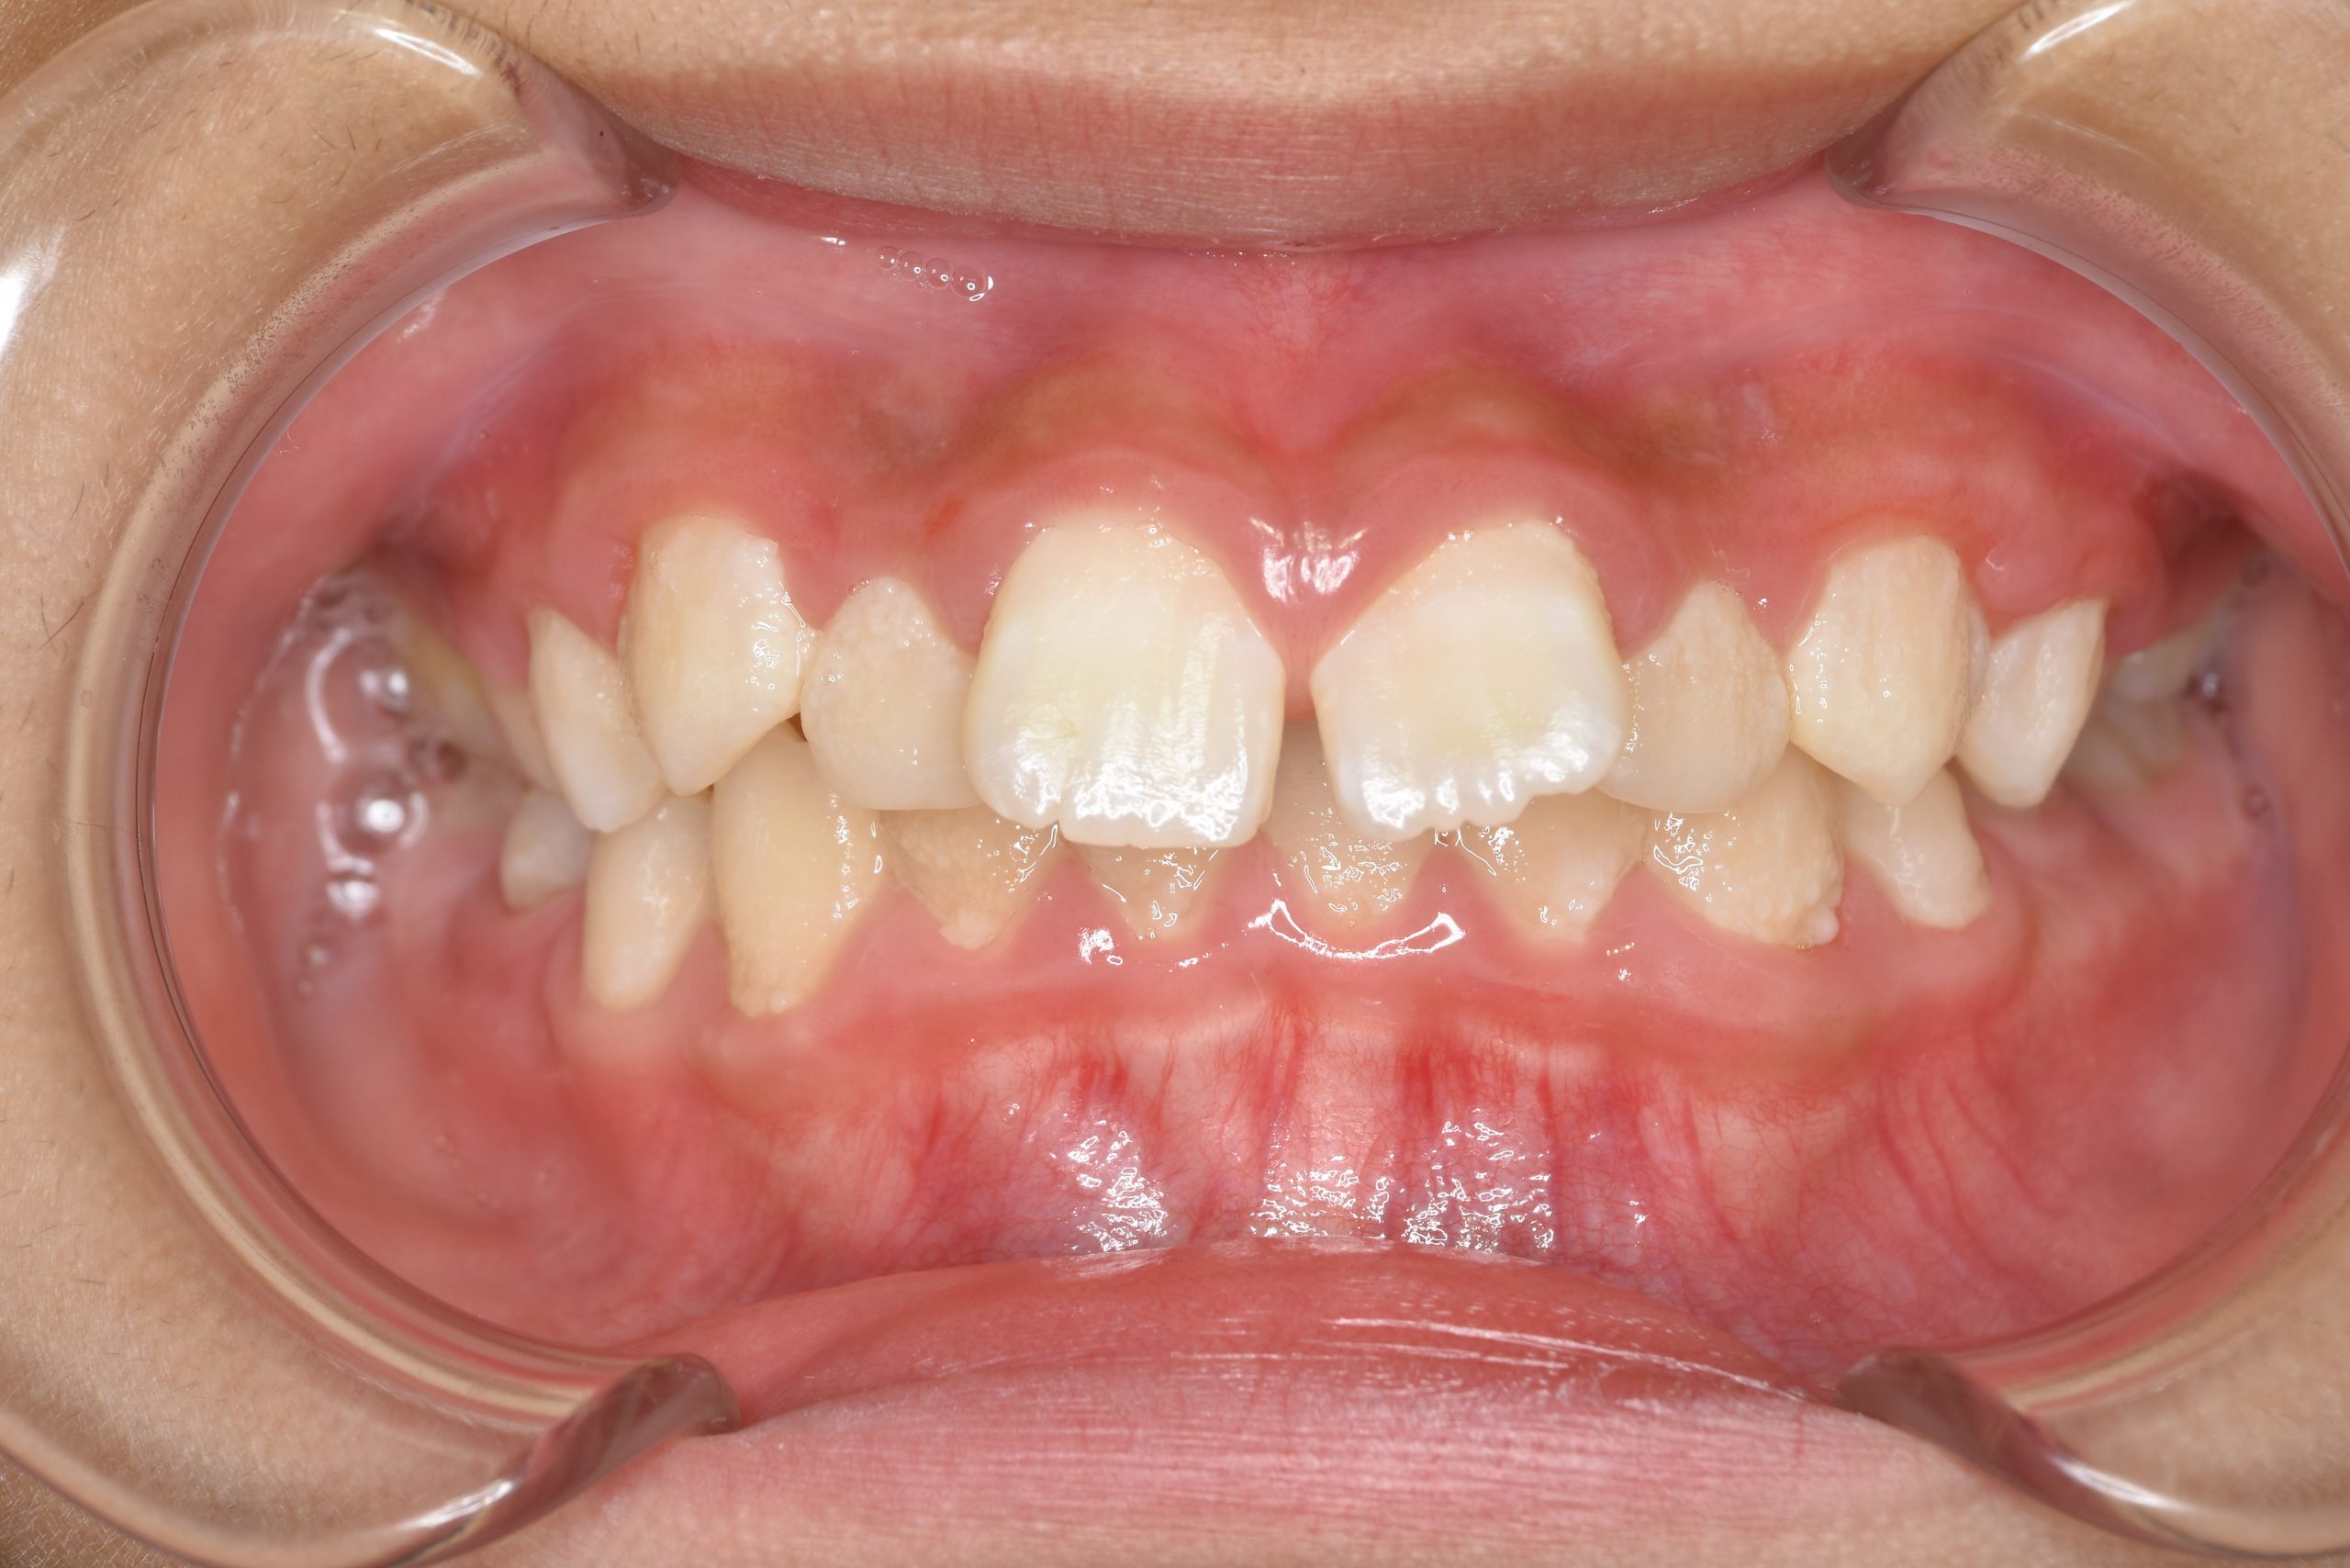

アフター

全顎ワイヤー矯正 症例_218

主訴 出っ歯|歯の隙間

施術内容 小児矯正1期治療

治癒期間 1年11ヶ月間

費用 465,400円(税込)